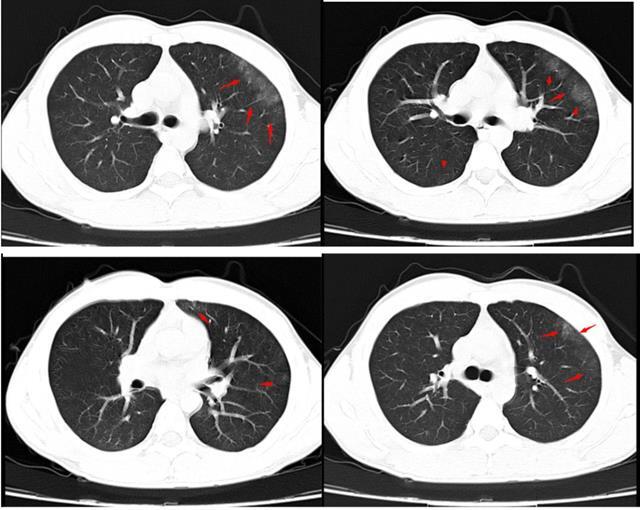

左肺严重挫伤

图片尺寸2667x2000